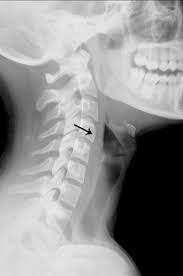

X Ray Of The Soft Tissue Neck Lateral View Showing The Mass Arrow Download Scientific Diagram from www.researchgate.net If the cancer cells look like they might have come from the larynx or hypopharynx, an endoscopic exam and biopsy of these areas will be needed. The appearance of throat cancer on the other hand depends on the part of the throat that is affected by cancer and the stage of its development. Surgical complications and side effects arising out of throat cancer treatment. Patches of rough, white, or red tissue. Treatment of throat cancer is based on its location, type of cancer, stage, and your child's health status. Throat cancer refers cancer that develops in your throat (pharynx) or voice box (larynx). Growths of tissue on the roof of. That is a typical sign of an infection originating.

The cancer can also appear as a hole in the bone. Oral cancer may present as: If you notice the second tooth from the left, you can see a dark aura surrounding the tip of the root. If this cessation of normal eating is accompanied by changes in the voice, contact your veterinarian immediately. Also, would throat cancer cause a lump like this growing on the outside of the throat/neck? Later stages indicate more advanced cancer, with stage iv being the most advanced. The tumor may be any size, but it has spread to: Throat cancer refers to cancer of the voice box, vocal cords, and other parts of the throat, such as the tonsils and the oropharynx. Tumors often show up as lighter gray than the surrounding tissue. Ameloblastoma isn't the same as jaw cancer or mouth cancer, head and neck cancer, nor even a bone cancer. That is a typical sign of an infection originating. And if this isn't cancer, could anybody offer an explanation as to what would cause a sore throat and growing lump? To evaluate respiratory conditions like asthma, bronchitis, and pneumonia, heart conditions, broken ribs, and to look for fluid and tumors within the chest cavity.

Lung cancer tumors look like white round circles on cxr. Tumors often show up as lighter gray than the surrounding tissue. The stage of throat cancer is characterized with the roman numerals i through iv. If you notice the second tooth from the left, you can see a dark aura surrounding the tip of the root. Ultrasound is useful in a few instances.